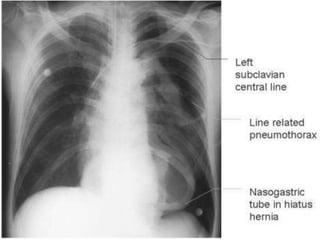

The tip of the left subclavian line lies in the

thoracic duct